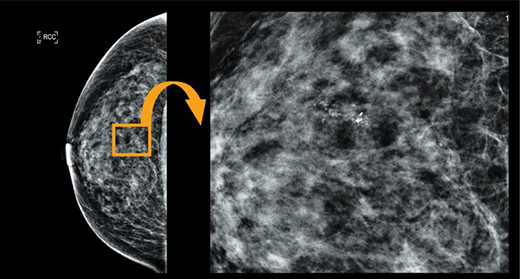

유방 촬영 검사에서 확인할 수 있는 석회는 일종의 ‘돌’ 입니다.

크기가 모래알처럼 작은 석회 여러 개가 집중적으로 모여 있을 때 ‘군집성 미세석회 병변’ 으로 표현하며 이는 유방암 또는 상피내암의 가능성이 있으므로 조직 검사가 필요합니다.

유방의 미세석회 병변은 대부분 초음파로도 안 보이고 육안으로도 안 보이며 만져지지도 않습니다. 오로지 유방촬영 검사에서만 보이기 때문에 조직 검사 방법이 복잡하며, 일부 유방외과에서만 시행할 수 있습니다.

또한, 유방촬영검사와 같은 영상검사에서는 판독의사의 경험과 실력만큼 해상도가 좋은 촬영기계를 사용하는 것도 중요합니다.